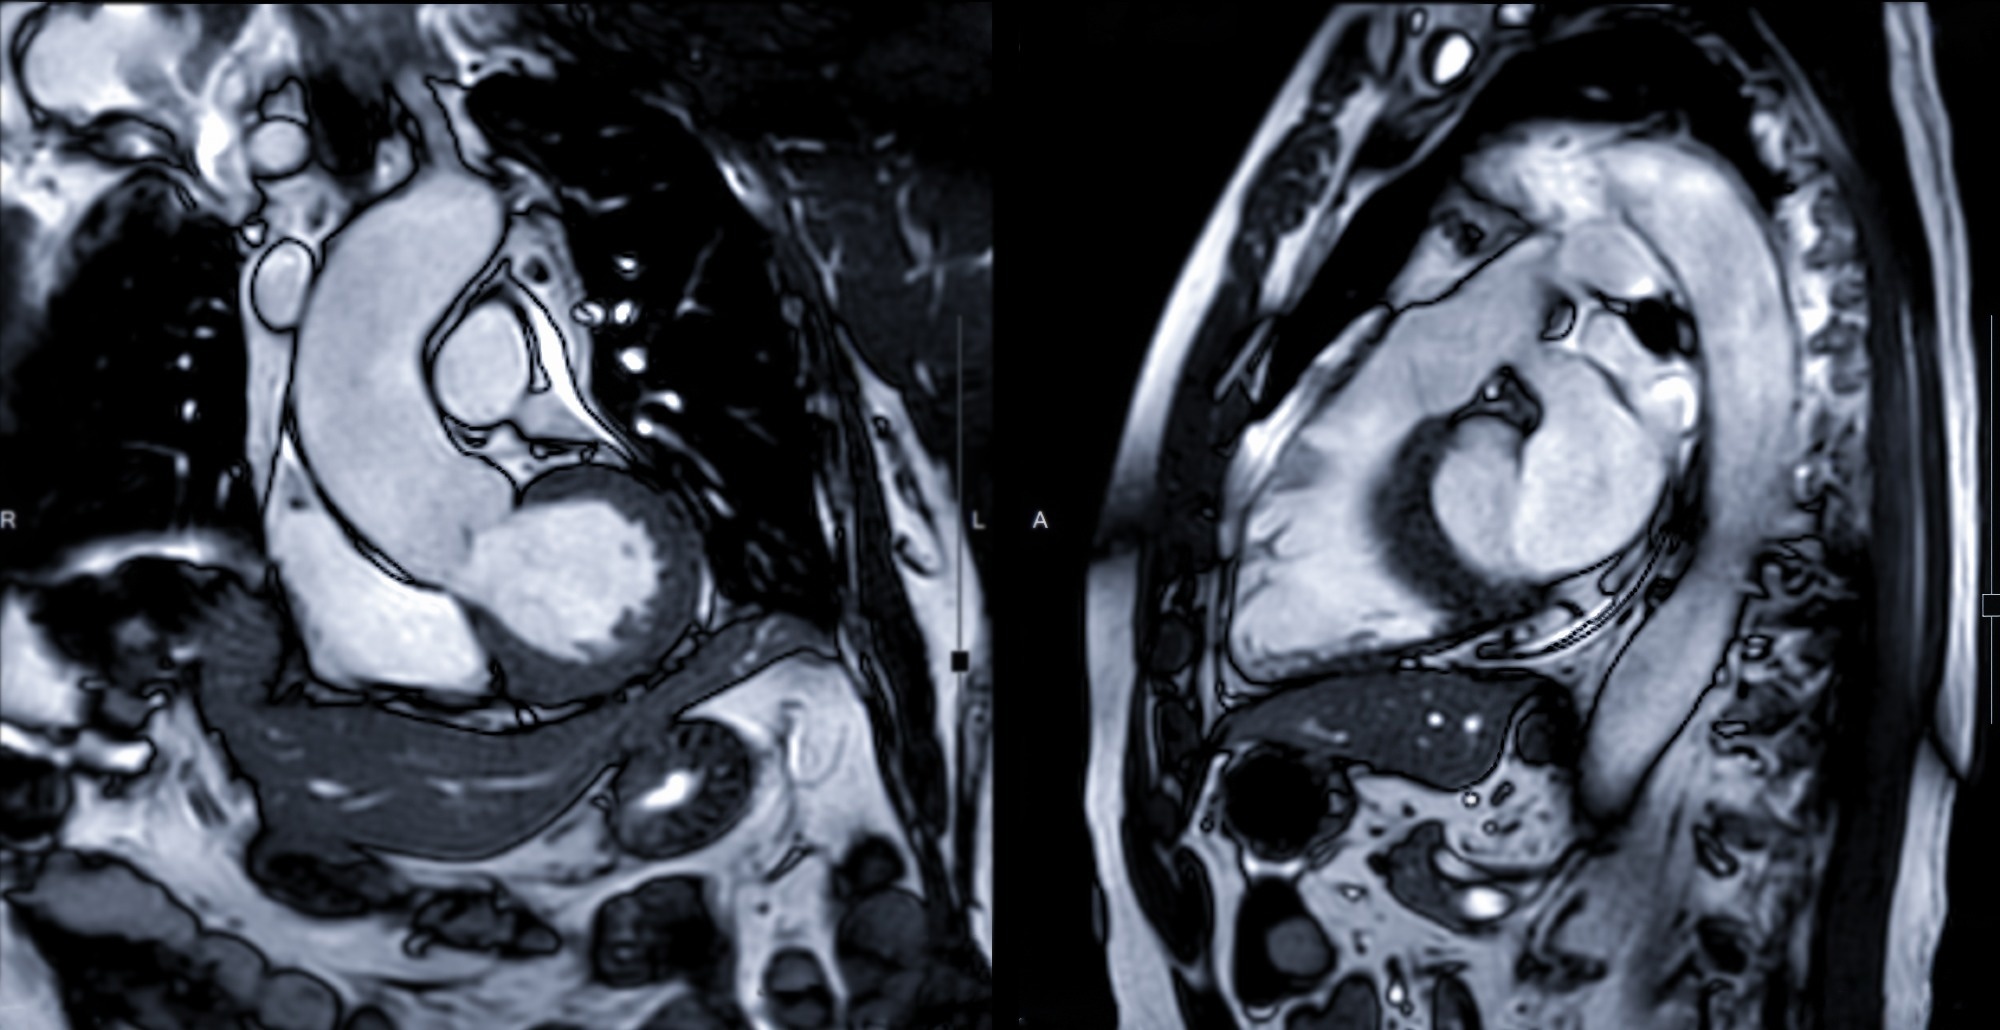

Study: Cardiac magnetic resonance findings in acute and post-acute COVID-19 patients with suspected myocarditis. Image Credit: Radiological imaging / ShutterstockStudy: Cardiac magnetic resonance findings in acute and post-acute COVID-19 patients with suspected myocarditis. Image Credit: Radiological imaging / Shutterstock

Cine-SSFP (cine steady-state free precession) images were analyzed for assessing wall motion alterations and cardiac chambers’ function and volumes. STIR (short-tau inversion-recovery) and T2 images were analyzed to assess the extent of edema, and LGE (late gadolinium enhancement) images were analyzed for myocardial scar identification. Native T1 and post-contrast T1 images were analyzed to assess the extracellular volume fraction. The type and extent of cardiovascular alterations in the CMR images were reported.